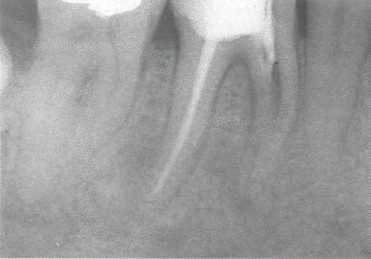

Рис. 706. Хирургическое эндодонтическое лечение.

Дистальный корень решено сохранить. Его корневой канал обработан инструментально, запломбирован гидроксидом кальция на 3 нед. и затем обтурирован гуттаперчей. Коронка зуба восстановлена стеклоиономерным цементом для герметизации устья канала.

Рис. 708. Рентгенологический контроль. После гемисекции медиальная часть зуба была удалена. На рентгенограмме определяют, полностью ли удалены нависающие края в области фуркации. Имеющийся нависающий край необходимо срезать. Слева: зуб после удаления медиальной части и нависающего дентина в области бифуркации.